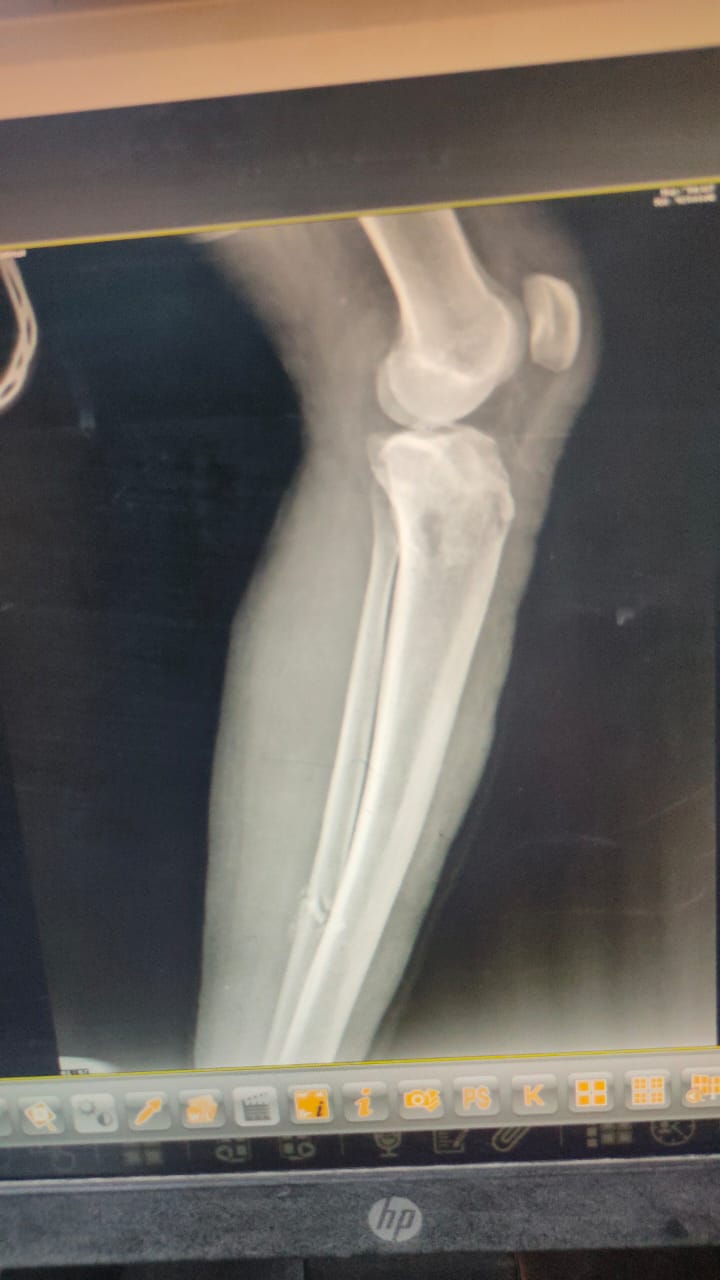

نجح فريق طبى مشترك من قسمى العظام وجراحة التجميل بمستشفى السنبلاوين العام في التدخل السريع لترقيع جلد الساق لمريض يعانى من كسرمضاعف بعد تركيب مثبت خارجي.

وأوضح الدكتور تامر مدكور وكيل الوزارة، أن الحالة تم تحويلها لمستشفى السنبلاوين وهى تعانى من كسر مضاعف مفتوح من الدرجة الثالثه بالساق اليسرى مع فقدان في الجلد والانسجة حيث تم تثبيت الكسر بمثبت خارجي مع الحفاظ على وضع الكسور ورد العظام وعقب ذلك جرى ترقيع للجلد من خلال أطباء جراحة التجميل.